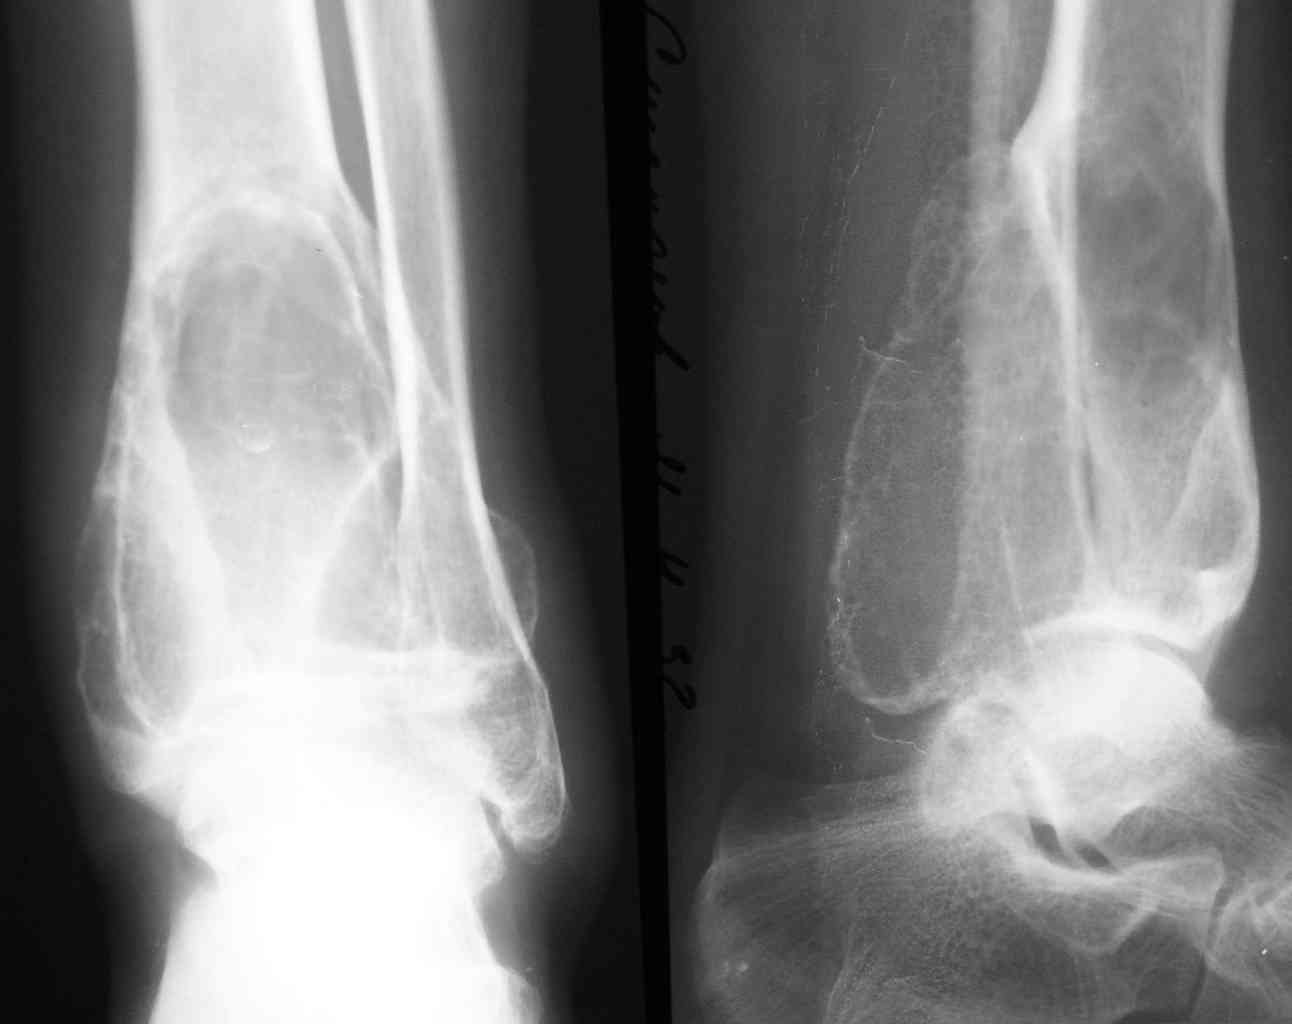

2-Пациент С.,32 лет,аневризмальная костная киста левой большеберцовой кости (Рис. 3,4), проходит лечение.

Rggrammi 32 letnego bolnogo skoree pohozhi na Gigantokletochnuy opuhol.

На представленных снимках рентгенологическая картина АКК не соответствует - в первом случае рентгенологическая картина (учитывая центральное расположение ) более соответствует солитарной костной кисте м.берц. кости, а в фаланге - кистовидная перестройка, во втором случае - гигантоклеточная опухоль